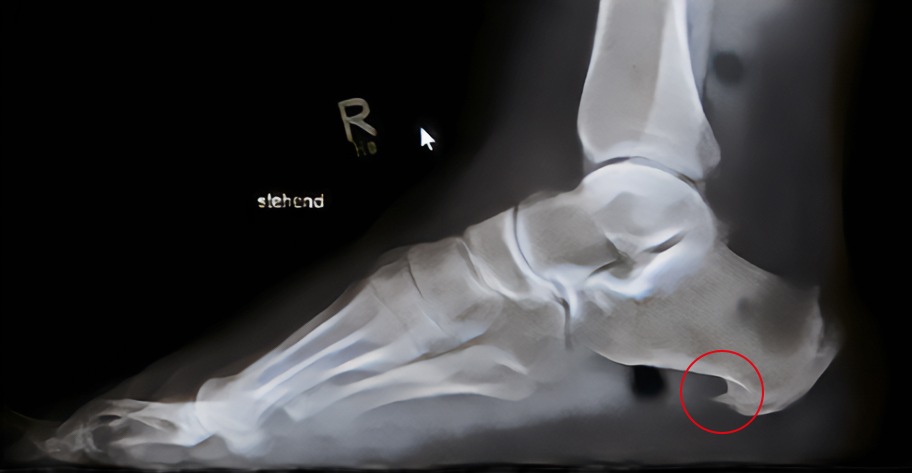

In unklaren Fällen können bildgebende Verfahren eingesetzt werden, wenngleich die Diagnose vornehmlich klinisch gestellt wird. Eine Röntgenaufnahme zeigt sehr zuverlässig, ob ein knöcherner Sporn vorhanden ist. Allerdings muss der - wie schon beschrieben - nicht mit den Beschwerden assoziiert sein. Bei Bedarf wird Ultraschall oder eine Kernspintomografie (MRT) durchgeführt, etwa um Weichteilstrukturen und Entzündungen genauer beurteilen zu können. Falls notwendig, kann eine Fußdruckmessung Aufschluss darüber geben, wie das Körpergewicht beim Stehen oder Gehen verteilt wird und wo es möglicherweise zu Fehlbelastungen kommt.

Bei dem eigentlichen Fersensporn handelt es sich um eine knöcherne Ausziehung am Fersenbein, die entsteht, wenn eine Sehne – beispielsweise die Plantarfaszie – über längere Zeit mechanisch überlastet wird. In diesem Bereich kann es dann zur Knochenneubildung kommen. Dieses „Extra-Knochenstück“ ist oft nur wenige Millimeter groß, kann aber mit erheblichen Beschwerden verbunden sein. Dabei ist zu betonen, dass die eigentlichen Beschwerden eher vom Ansatz der gereizten Faszie als von der Knochenausziehung ausgehen.